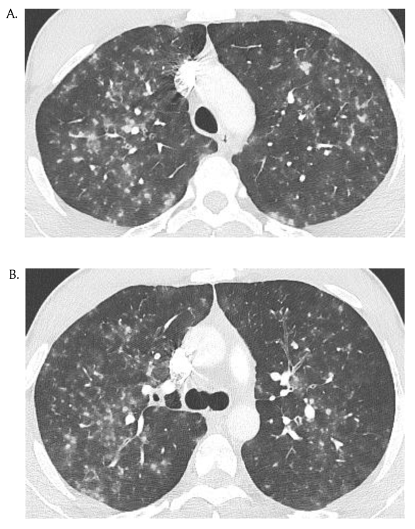

图4 21岁女性有水痘暴露史,表现为头痛、肌痛、关节炎、无力、咽痛与纳差,CT示两肺多发结节。(Shalaby T,et al. Br J Hosp Med (Lond). 2015)

图4 37岁既往体健男性因发热、干咳与胸部弥漫性皮疹2天就诊。

图5 同一病人,CT示两肺弥漫性GGO。(Miyokawa R, et al. J Gen Intern Med. 2019)

图6 25岁男性,因咯血急诊,3天前诊断水痘,被其3岁女儿传染,CT示两肺多发性边缘模糊的小叶中央型结节与伴外周GGO的微结节,以上叶为主。(Médart, L, et al. Varicella Pneumonia.)